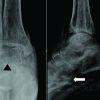

An elderly lady of around 60 years came to our hospital with severe pain in her left index finger base after she got injured while she was trying to hold a grip very forcefully. The left-hand index finger was kept semiflexed position in the proximal interphalangeal joint and slightly extended at the metacarpophalangeal joint. The index finger base was very tender and there was a visible dimple near the A1 flexion pulley area of the left index finger. There was no open injury. X-rays were done and it showed that 2nd MCP joint was dislocated with a small chip fracture of the 2nd metacarpal head. The dislocation was irreducible and it needed an open reduction, we approached through the dorsal approach to the MCP joint. After skin incision and carefully separating the extensor tendons, the joint capsule was identified, a longitudinal capsulotomy was done and the trapped volar plate was freed with a small curved periosteal elevator, after relocating the trapped volar plate, the dislocated phalanx could be easily relocated to its original position. The reduction was checked both clinically and radiologically with c-arm images. The small bone fragment was excised and the capsulotomy was closed with 2–0 vicryl. After checking the hemostasis, the wound was closed. The joint was splinted with MCP joint at 30° flexion, and stitches were removed after 2 weeks, range of motion exercises were started after 3 weeks, and patient was advised to limit the last 20° extension of the 2nd MCP joint.

In Fig. 2, the volar plate is trapped between the metacarpal head and the dislocated proximal phalanx, and here, the dislocated proximal phalanx is staying almost parallel to the metacarpal shaft. The first clinical condition is termed as simple MCP joint dislocation, as here there is no obstruction of volar plate, and the dislocation can easily be reduced by closed methods. However, the second clinical scenario is called as the complex or the irreducible MCP dislocation as here the intervening obstructing volar plate blocks the dislocation by closed methods, and it needs open method to release the obstructing volar plate to achieve relocation [3]. The distinctive anatomy of simple and complex MCP joint dislocation is also evident in radiographs, as in the first case, the proximal phalanx almost lies perpendicular to the metacarpal shaft, and in the second case, the dislocated proximal phalanx lies almost parallel to the metacarpal shaft, the so-called bayonet appearance. This helps to alert the clinician about the nature of the dislocation. The complex dislocation of the metacarpophalangeal joint dorsally is called the Kaplan dislocation (Fig. 3-5). Although it can involve any fingers, the most common is the index finger MCP joint [4]. (Fig. 6). In his 1957 article, Kaplan described in detail the various anatomical structures around the MCP joint, especially emphasizing the button holing of the metacarpal head through the surrounding soft tissues and the interposition of the volar plate between the metacarpal neck and proximal phalanx base making close reduction very difficult [3]. The surrounding soft tissues produce a noose-like effect around the dislocated metacarpal if repeated closed reduction is tried without understanding the pathology [5]. The capsule of the MCP joint is strengthened by the volar plate ventrally. The radial side of the joint is reinforced by the lumbrical muscles and the ulnar side is strengthened by the flexor tendons of the digit along with pre-tendinous bands [5]. The superficial transverse ligament and the natatory ligament tighten around the metacarpal neck on repeated forceful reduction attempts, along with the extrinsic and intrinsic muscle tendons causing the noose effect as proposed by Kaplan [6]. There are various approaches described in literature to address this problem. Kaplan himself was fond of the volar approach [7] (Fig. 7 and 8). The volar approach approach helps to directly address the main interposing structure, the volar plate. It involves applying a curvilinear incision centering over the MCP joint. The A 1 pulley is often needed to be released to gain access to the dislocation. Mostly the entrapped volar plate can be freed without releasing it. However, it requires meticulous dissection as the dorsal digital artery and the digital nerves lie very close. Here, the volar plate remains intact, so chances of late dislocation or instability are minimal [8]. Becton et al., in their article proposed a simplified direct dorsal approach to treat this complex injury. Here, the dislocation is approached through the dorsal aspect by a curvilinear incision centering over the MCP joint. After releasing the skin and subcutaneous tissue, the joint capsule is approached. After releasing the joint capsule longitudinally, a white shining structure is found, that is the intervening volar plate, if attempts to slide the volar plate are not successful, then its needed to incise the volar plate longitudinally and slide it away to achieve reduction. Sometimes, the deep transverse collateral ligaments may also be needed to be released. Becton et al. also stated that the management of osteochondral fractures is easier by the dorsal approach. If the fragment is very small, it can be discarded or stitched with 2-o vicryl or if it is a lager fragment then it can be fixed with small transcutaneous k wire which can be removed percutaneously after 3 weeks [9]. Sandeep et al. in their case report described a percutaneous needling technique to incise the interposed volar plate and thus achieve a closed reduction [10].